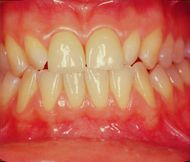

A first clinical occlusal examination shows a functional occlusal class III with sliding in protrusion in reaching the maximum intercuspidation. On palpation, the masseters, temporals, and external pterygoids on both sides were tender. No balance and gait disturbances, no vertigo, no tinnitus but as our routine we immediately performed trigeminal electrophysiological tests in order to avoid any structural involvement of the trigeminal Central Nevous System (tNCS). As already explained in the chapter concerning the 'Balancer' patient with Meningioma in which the interference EMG examination performed by the dental colleagues did not give indications of organic pathology of the tNCS in our Diagnostic Center we only perform Evoked Potentials and the battery of trigmeinal reflexes. In this chapter, taking into account the clinical situation, we have bypassed the purely dental context as, after an initial objective examination, the malocclusive disorder is striking but not certain (figure 2).